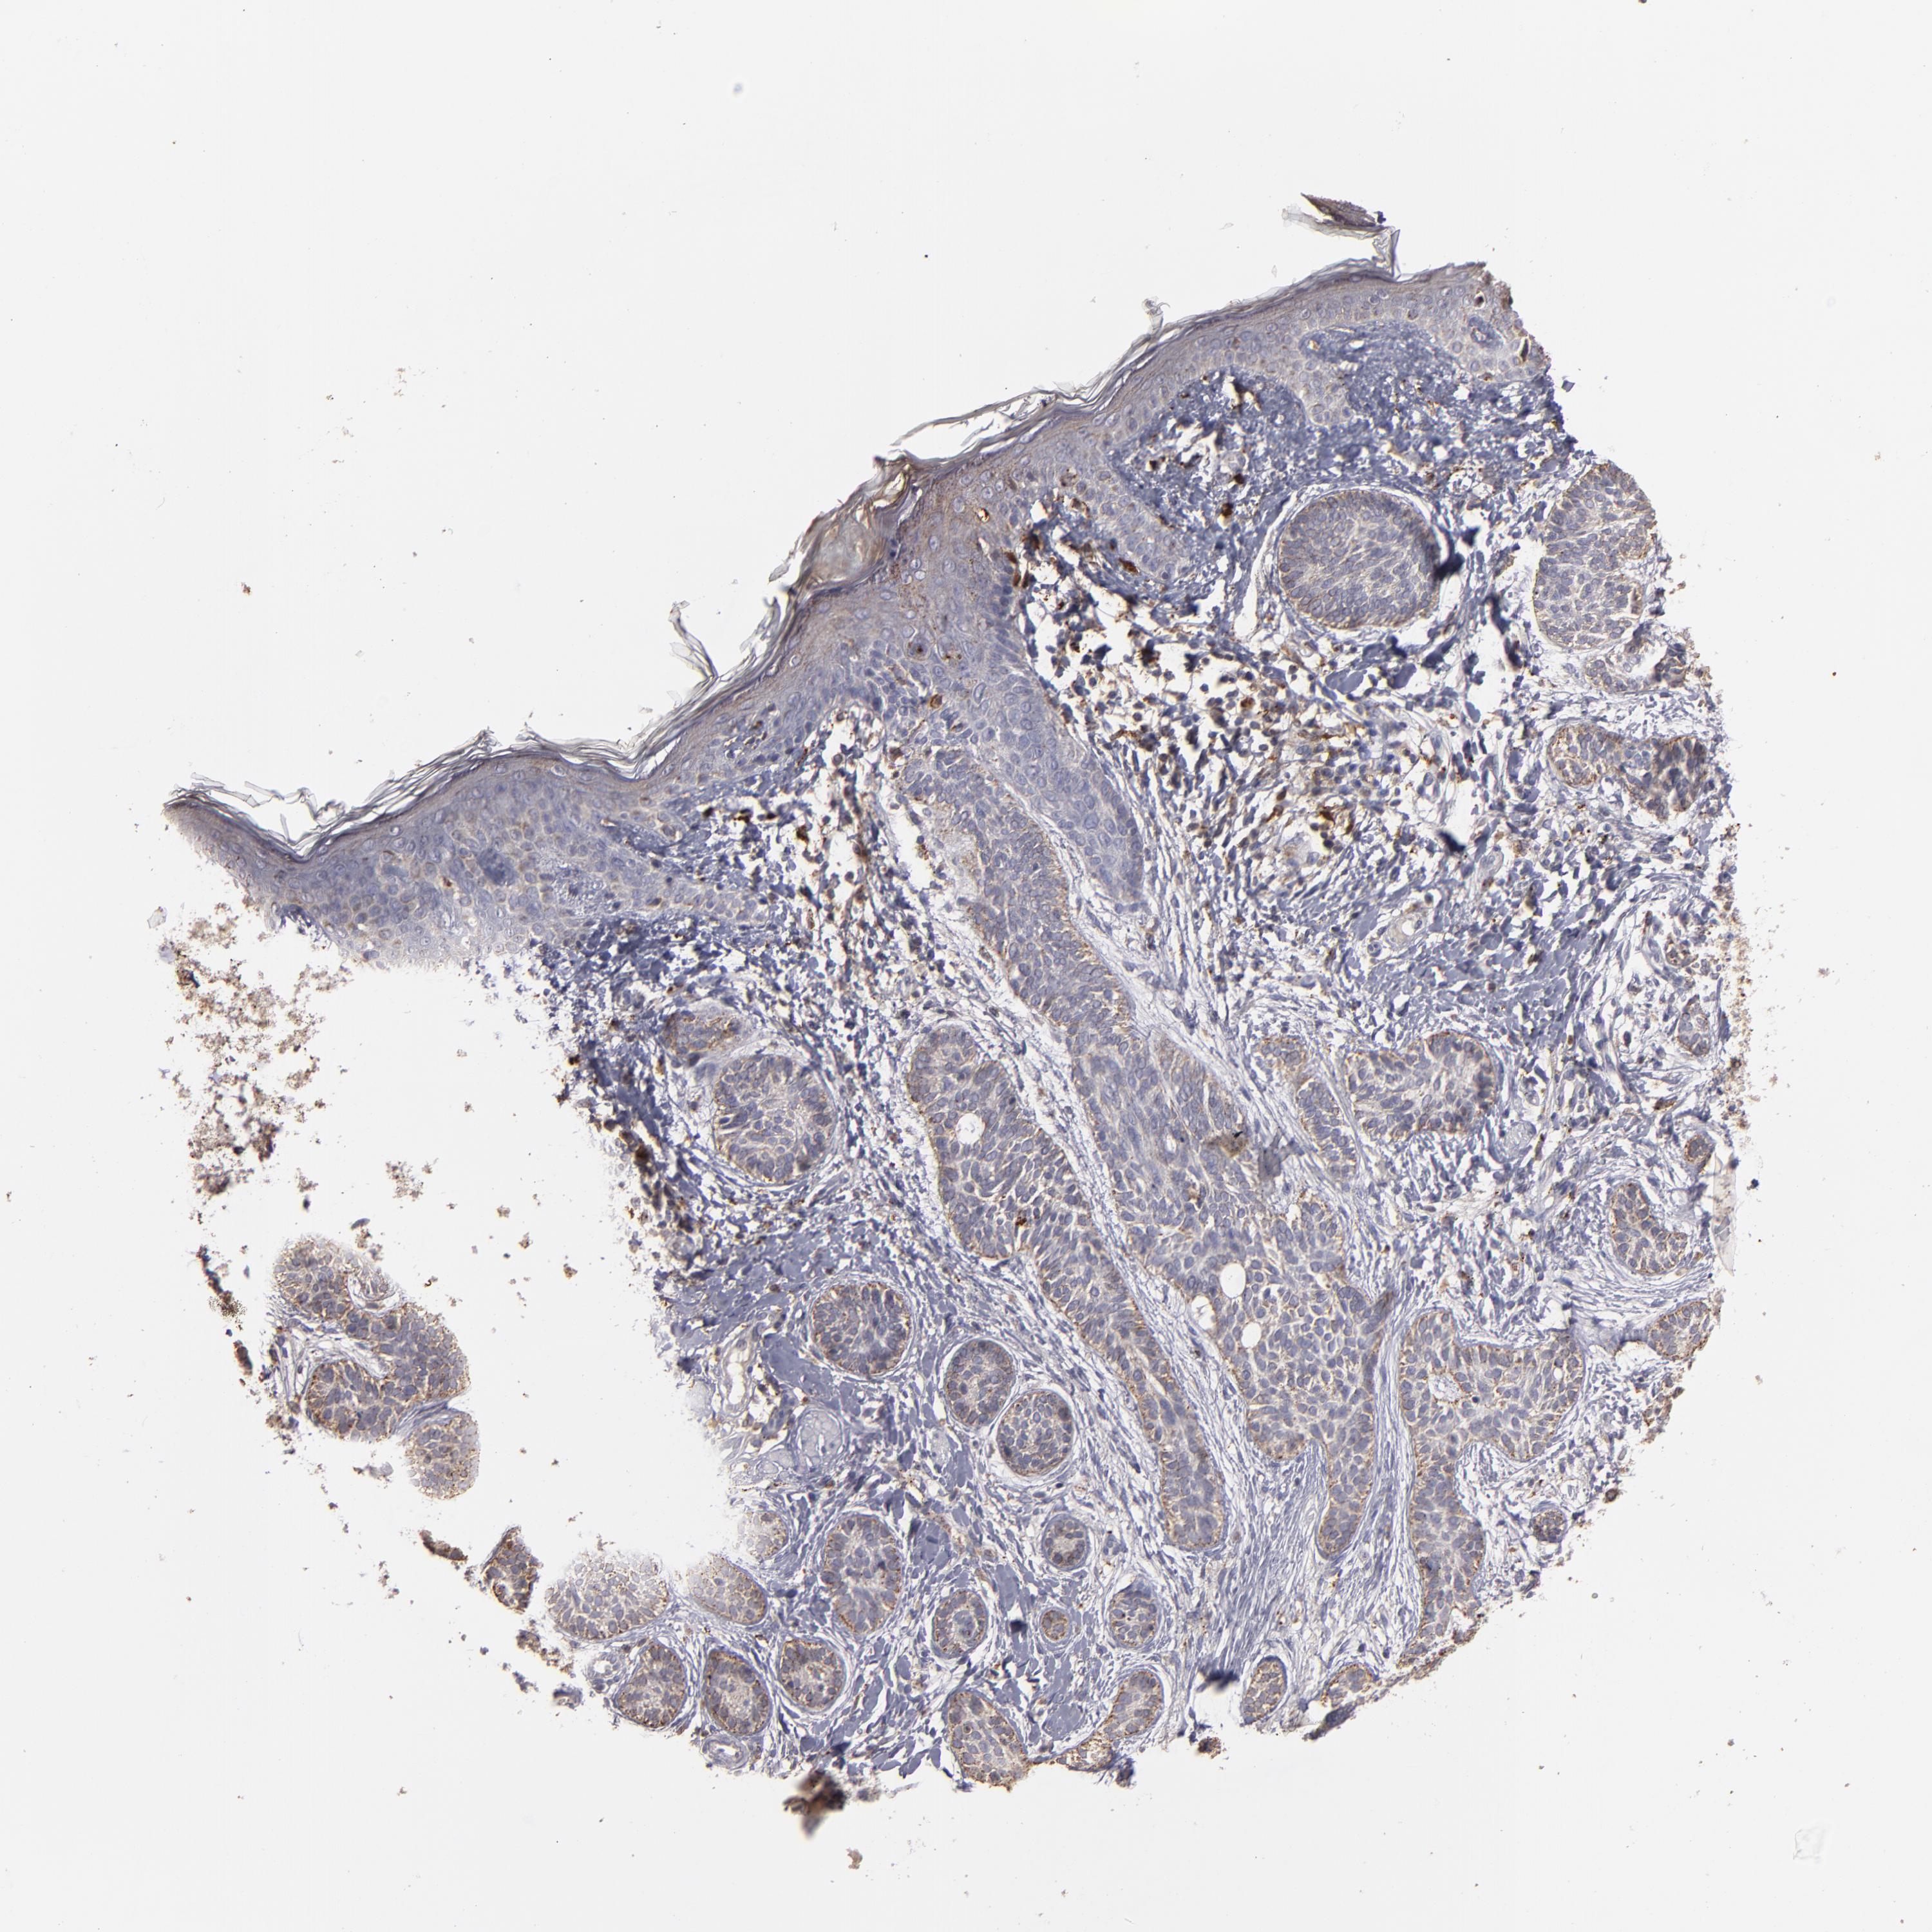

SKIN CANCER - Protein expressioni

A mouse-over function shows sample information and annotation data. Click on an image to view it in a full screen mode. Samples can be filtered based on level of antibody staining by selecting one or several of the following categories: high, medium, low and not detected. The assay and annotation is described here.

Each image is clickable and will lead to virtual microscopy that enables deeper exploration of all samples and also displays staining intensity scores, fraction scores and subcellular localization as well as patient and tissue information for each sample.

Antibody HPA001852

Antibody CAB009593

Squamous cell carcinoma, NOS

Basal cell carcinoma